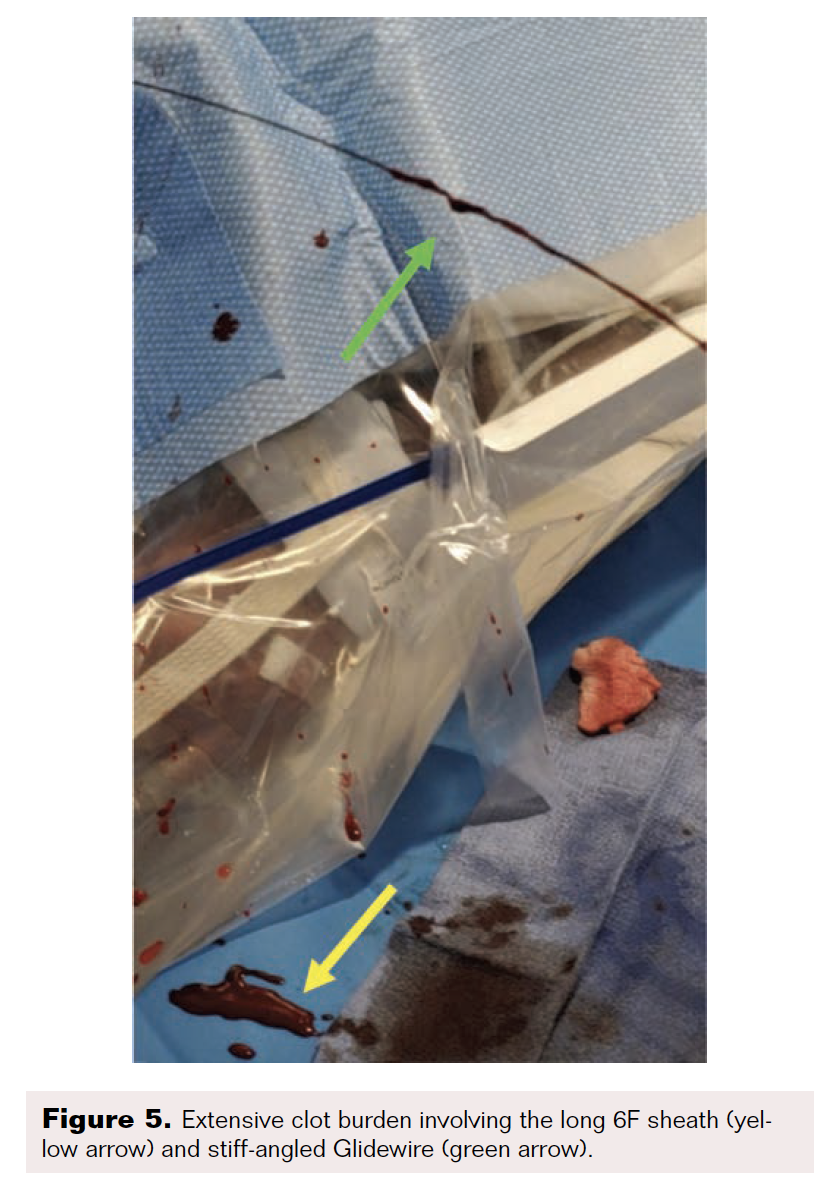

After the wire exchange, we attempted to aspirate, then flush, the 6F sheath with heparinized saline. After multiple failed attempts at sheath aspiration, we suspected a clotted arterial sheath and immediately proceeded to sheath exchange with a new 6F 45 cm sheath. Cautious to maintain wire position, the sheath was successfully exchanged. Saline flushing of the removed sheath resulted in expulsion of extensive clot burden (Figure 5). Repeat ACT confirmed therapeutic anticoagulation. The procedure concluded with percutaneous transluminal angioplasty followed by stenting of the SFA with BioMimics 6 x 150 mm stents (Figure 6). Final angiography demonstrated brisk flow through the SFA, popliteal, and anterior tibial arteries with no evidence of distal embolization (Figure 7 and Figure 8).